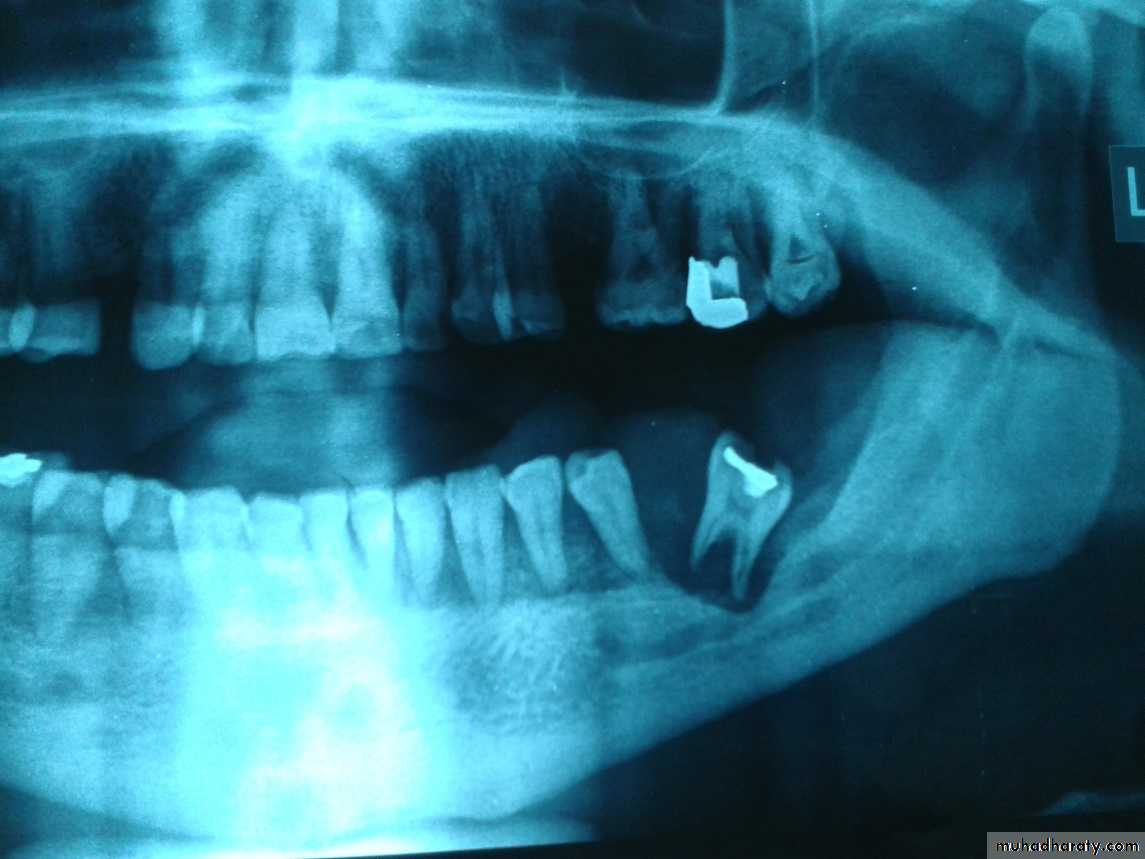

Raioraghical examination may demonstrate unlocular or multilocular types. Unilocular ameloblastomas may be confused with benign cysts. The tumors frequently absorbs the alveolus surrounding ,the roots of teeth and may absorb root ends.

which appears as an areas of circumscribed being bony new growth. osteomas arising from the inner surface of bone cortex. Tumor of this kind consist of dense cortical bone extending into the spongiosa of The jaw. They can be seen in the X-Ray as circumscribed dense bony tumors .which appears as a radiopaque shadow.

These tumors of embryonic tissue origin developing from immature primitive bone or cartilage cells. the myxoma may simulate a cystic lesion because of its honeycomb appearance in the x-rays, Expansion of the bone cortex occurs with the appearance of mucoid material replacing bone architecture.The chondroma arises from aberrant fetal cartilage in specific regions of the mandible such as the symphysis and coronid and condyloid process. Myxoma and chondroma may be detected clinically by pain swelling and limitation of motion. these tumors grow slowly they are extripated surgically.

The central giant cell tumor is a benign neoplasm developing in the bone of cartilaginous origin the symphysis and the angles of the mandible and the canin fossa of the maxilla are typical locations . these tumors occur in the second or third decade of life with trauma as the suspected factor. pain and swelling of the mandible with occasional fractures. Occurs whenever the tumor reaches a large size,X-Rays show no uniform clear-cut picture of central giant cell tumor since the growth appears as multicystic areas with irregularly outlined , fine trabeculations . the teeth are frequently loosened these tumors destroy spongy bone and tend to thin out the cortical bone to a frail shell thus lead to ultimate perforation . the tumor tissue is soft and highly vascular and tends to undergo free hemorrhage when traumatized.